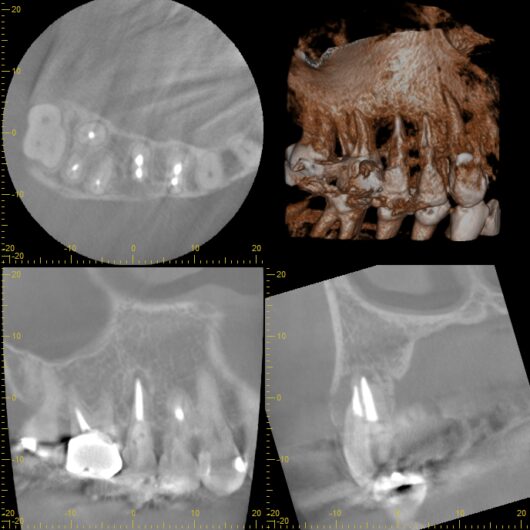

初診時

CT撮影 破折しているのがわかる↑

精密なCT診断とシミュレーション

この患者さんの場合、幸いなことに骨欠損がそれほど大きくなかったため、

抜歯即時インプラントの適応となりました。

治療を始める前に、最新のCT撮影を行い、コンピューター上で綿密なシミュレーションを

実施しました。骨の厚み、高さ、密度、神経や血管の位置など、

あらゆるデータを三次元的に分析します。このシミュレーションにより、

インプラントを埋入する最適な位置、角度、深さを1ミリ単位で計画することができるのです。